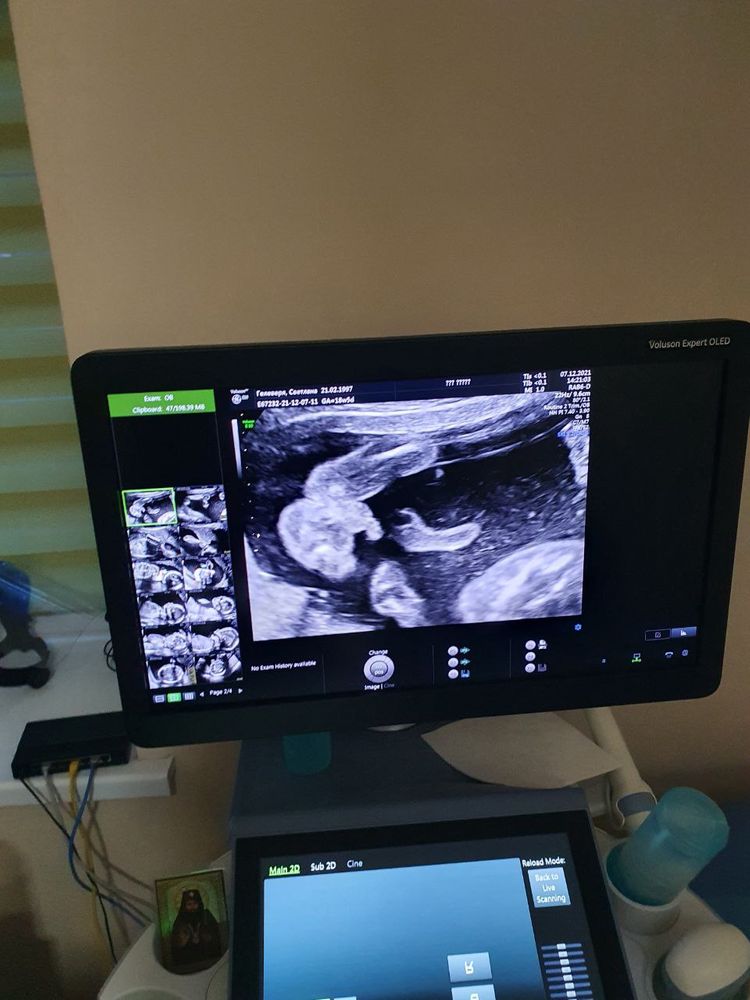

Мальчик или девочка

Вот наш) так что у вас тоже мальчуган 😁 Изображение

Без сомнения виден писарчук

Без варианта тут парень))

Мальчик 👶🏻 😍

Это пацан, видно же машонку. Я была на узи в 20+ недель для определения пола, мне точно такое же фото показывали:)

Мальчик)) у меня с дочкой, прям было видно пирожок, а тут бубенчики😂😜

У девочки губки, две полосочки. А тут на мошоночку похоже))